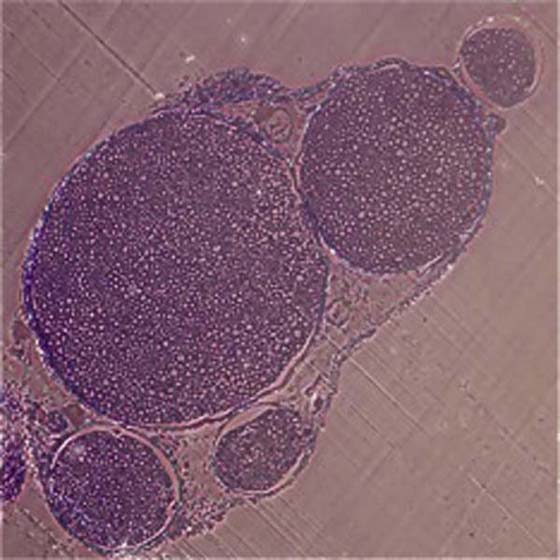

Fascicular patterns are divided into the following three types: monofascicular, oligofascicular, and polyfascicular.1 Monofascicular patterns consist of one large fascicle, whereas oligofascicular patterns consist of a few fascicles; polyfascicular patterns consist of many fascicles of varying sizes that can be arranged with or without groupings of fascicles (Fig. 42-3). Nerves found in the upper arm are routinely polyfascicular. In its course from the upper arm to the fingertips, a peripheral nerve undergoes changes from a polyfascicular pattern in the upper arm, oligofascicular in the elbow region, and monofascicular in the hand and fingers. For example, the ulnar nerve is polyfascicular as it exits the brachial plexus until just before the elbow, at which point it becomes oligofascicular. After the division into the motor branch at the wrist, the pattern is monofascicular. These patterns may help to determine which type of nerve repair is appropriate for a particular nerve injury. In surgical nerve repair, proper identification of fascicular arrangement is crucial to maximizing the chances for a successful outcome.

images

Figure 42-3 Toluidine blue–stained polyfascicular cross section of a normal murine sciatic nerve (×10).